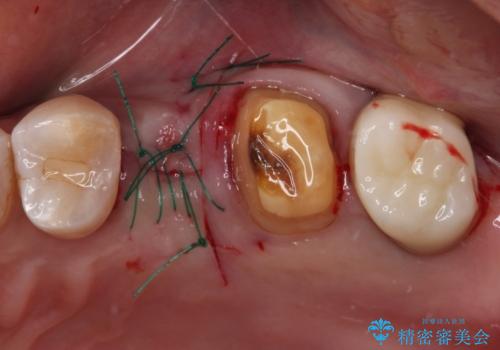

仮歯に置き換えた時点で歯肉からの出血は収まり、不快感が改善されました。

右下は、残存歯の状態があまり良くなかったため、今後抜歯となったことを想定して、最後臼歯のインプラントを決定しました。